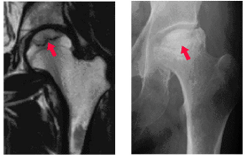

大腿骨頭壊死を診断するための主な検査は、レントゲンとMRI検査です。

早期の場合はレントゲン写真だと診断がつかないことが多いため、少しでも疑いがあればMRI検査を行います。